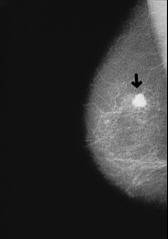

Escargots against breast cancer with blood group A

Escargot (Helix pomatia) contains a lectin which is well working in the body of blood group A and is fighting well cancer cells which are behaving similar to body cells of blood group A (4 Strategien, p.111).

<Escargot (Helix pomatia) contains - as we will see in chapter 10 [see cancer according to blood groups] a highly effective lectin which is attracting and agglutinating cancer cells of the two most distributed types of cancer in the body of blood group A. This is a positive kind of agglutination because this lectin is eliminating the ill cells.> (4 Strategien, p.111)

-- breast cancer, x-ray photo: http://www.prof-obwegeser.at/brustkrebs.htm